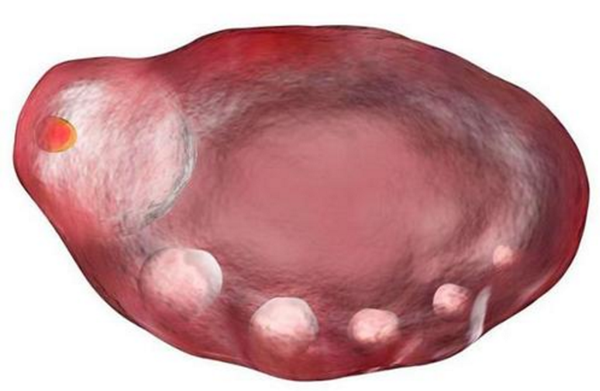

促性腺激素释放激素类似物(gonadotrophin releasing hor泰国试管婴儿生男孩mone analogue,GnRHa)是一种人工合成的促性腺激素释放激素,泰国试管婴儿专试管婴儿家说明中讲述其种类包括促性腺激素释放激素激动剂 (gonadotropin releasing hormone agonist试管婴儿移植后,GnRH-a)和促性腺激素释放激素拮抗剂 (gonadotropin releasing hormone antagonist,GnRH-A)。目前这两类激素,尤其 GnRH-a,在临床上被广泛用于多种妇产科疾病的治疗。现就 GnRH-a 和 GnRH-A 的特点和应用进行概述。